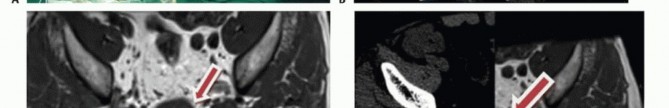

التصوير المقطعي المحوسب والرنين المغناطيسي

- التصوير المقطعي المحوسب (CT): يُعد بتقنية التباين الوريدي الأسلوب الأمثل لتقييم مدى انتشار الورم في العظم وتدميره، والتكلسات المحتملة، والموقع التشريحي، والإمداد الدموي، وعلاقة الورم بالأعضاء الحشوية. يساعد في التفريق بين الأورام الحميدة والخبيثة.

- التصوير بالرنين المغناطيسي (MRI): بتقنية التباين، يُعد حاسمًا لتصوير الأنسجة الرخوة ومدى انتشار الورم فيها، وعلاقته بالأنسجة المحيطة (مثل الأوعية الدموية والأعصاب والعضلات والأعضاء الحشوية). يُعتبر الأسلوب الأمثل لتصوير الأنسجة الرخوة نظرًا لقدرته الفائقة على التمييز مقارنةً بالتصوير المقطعي.

يُعد التخطيط الدقيق قبل الجراحة أمرًا حاسمًا لنجاح العملية. يقوم الأستاذ الدكتور محمد هطيف بمراجعة شاملة لجميع صور ما قبل الجراحة (الأشعة السينية، التصوير المقطعي، الرنين المغناطيسي، تصوير الأوعية الدموية) لتحديد خطة جراحية واضحة وتقييم الدواعي والمخاطر.